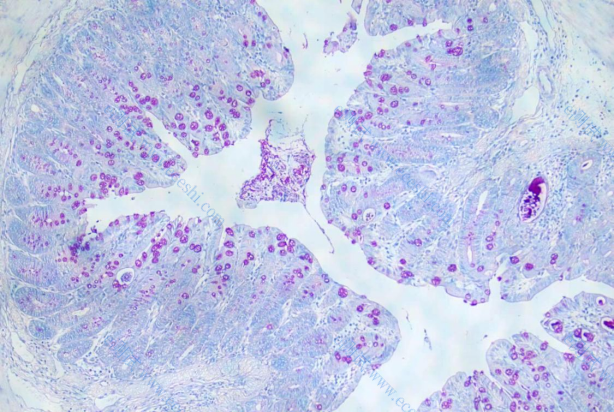

1、HE染色

6、pas 染色